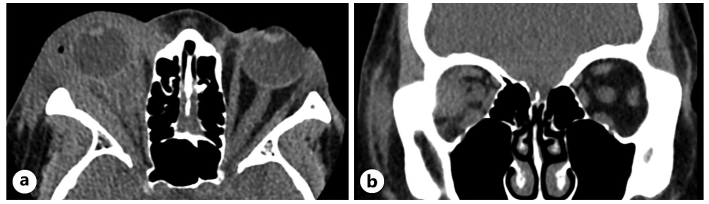

• 病情转折:当激素减量至 40 mg/day 以下时,症状难以控制;减量至 20 mg/day 时,患者自觉无效并停药。停药 1个月后复查,右眼眶周肿胀明显加重。复查 CT(图 2)显示右侧眼眶软组织肿胀恶化,外直肌显著增大并累及肌腱端,但仍未形成典型肿块。

图2 停用激素后的复查 CT:(A)轴位及(B)冠状位显示右侧眶周软组织肿胀明显加重,眶内脂肪弥漫性条索影,右侧外直肌显著肿大。